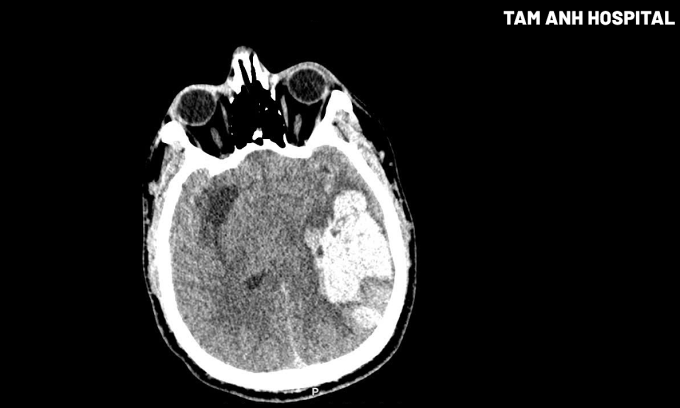

Kết quả chụp CT cho thấy bệnh nhân có ổ tụ máu nhu mô não thùy thái dương đỉnh trái kích thước 40×45×81 mm, chèn ép não thất cùng bên, lệch đường giữa 7 mm sang phải, thoát vị hồi hải mã trái (một phần hồi hải mã ở thùy thái dương trái bị đẩy lệch xuống dưới và vào trong, chui qua dưới liềm đại não). Tiến sĩ, bác sĩ Nguyễn Đức Anh, Trưởng khoa Ngoại Thần kinh Cột sống, chẩn đoán anh Đức xuất huyết não do tăng huyết áp giờ đầu, tình trạng rất nặng.

Hình ảnh khối máu tụ ở thùy thái dương đỉnh trái của người bệnh qua phim chụp CT. Ảnh: Bệnh viện Đa khoa Tâm Anh Hà Nội